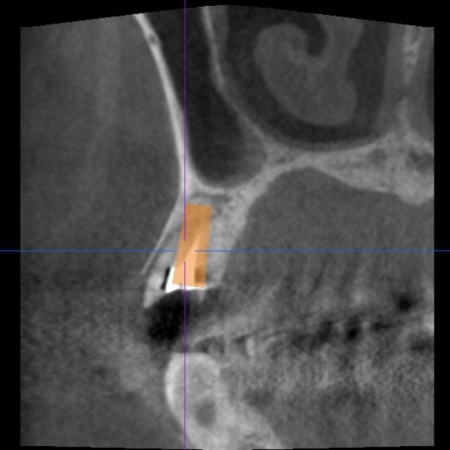

| 診断 | 拝見したところ、左上奥歯(第1小臼歯)は歯の上の部分である歯冠が折れ、歯根のみ残っている状態でした。 また、左下奥歯(第2小臼歯)には被せ物が装着されています。 レントゲン撮影をして痛みの原因を詳しく検査したところ、左上下奥歯の歯根が割れており、その影響で痛みが出ていると考えられました。 歯根が割れた歯は温存が難しく、このまま放置すると炎症が広がって周囲の歯に悪影響を及ぼすおそれがあるため、抜歯せざるを得ない場合があります。 以上のことから、温存が難しいと判明している左上奥歯は抜き、左下奥歯は被せ物を取り外して内部を確認したうえで、適切な処置を行うことが望ましいと診断しました。 |

| 行ったご提案・治療内容 | 診断結果をお伝えし、患者様の了承を得たうえで左下奥歯の被せ物を外したところ、レントゲン検査での診断どおり、歯根が割れていることが確認できました。 そのため、患者様には左上下奥歯とも温存が難しい旨を説明し、抜歯に同意いただきました。 患者様は、以前当院で人工歯根を顎の骨に埋入して歯を装着するインプラント治療を受けていたため、今回も左上下奥歯ともインプラント治療を希望されています。 メリット デメリット 改めてメリットとデメリットをしっかりお伝えしたところ、インプラント治療に対する不安はないとのことで、治療に同意いただきました。 まず、左上下奥歯を慎重に抜きます。 インプラント手術後は経過観察を行い、インプラントが顎の骨に結合したことを確認したら、インプラント上部に取り付ける人工歯を作製するために精密な型取りを実施します。 後日、完成した人工歯をインプラントに装着し、使用感や見た目に問題がないことを確認して、治療を終了しました。 |